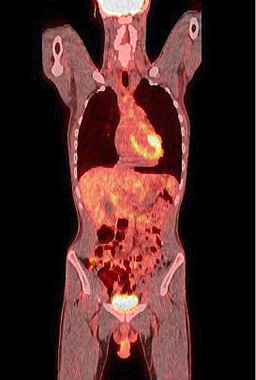

The plain radiograph showed signs of small bowel obstruction (Figure 1).

One year after the operation, a PET/ CT scan performed showed normal distribution of F-18 FDG and no signs of residual intraabdominal tumor (Figure 9). In the present period, the patient is disease free.

Figure 9. A normal finding of post-transplant PET/CT Scan